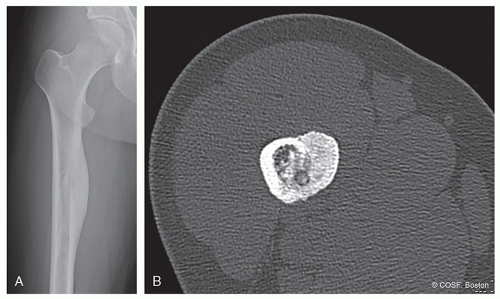

How is the bone responding to the tumor: margination, periosteal reaction? (Figures 41.1,41.2,41.3,41.4,41.5,41.6,41.7,41.8,41.9)

Where is the tumor in the bone?

Epiphysis: chondroblastoma in skeletally mature, giant cell tumor in adult (see Figures 41.2 and 41.8)

Metaphysis: Benign—nonossifying fibroma, osteochondroma, unicameral bone cyst, aneurysmal bone cyst, chondromyxoid fibroma (see Figure 41.1)

Malignant: osteosarcoma chondrosarcoma, undifferentiated pleomorphic sarcoma of bone (see Figure 41.3)

Diaphysis: Ewing sarcoma (see Figure 41.4)

Osteoid osteoma is usually cortically based in any part of the bone (see Figure 41.5); LCH can mimic almost anything

Are there any specific characteristics: “Ground glass” of fibrous dysplasia (see Figure 41.6), “popcorn” calcification of a cartilage tumor (see Figure 41.7), “stippled calcification” in a chondroblastoma (see Figure 41.8), ivory vertebra—lymphoma, leukemia, Paget disease, vertebra plana in LCH